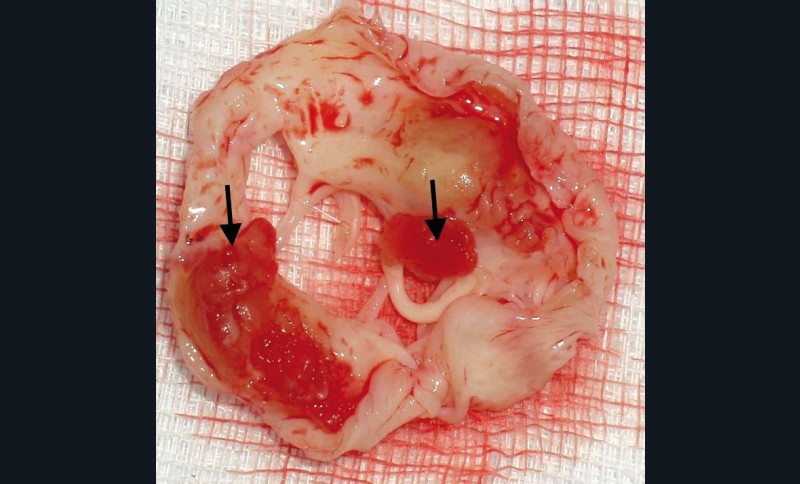

Le dépistage et le traitement des foyers infectieux bucco-dentaires ont toujours été une préoccupation chez les patients présentant une cardiopathie valvulaire en raison du risque d’endocardite infectieuse. Les principales lésions valvulaires sont des mutilations à l’origine de fuites aiguës et des végétations responsables de complications emboliques (fig. 1 et 2).